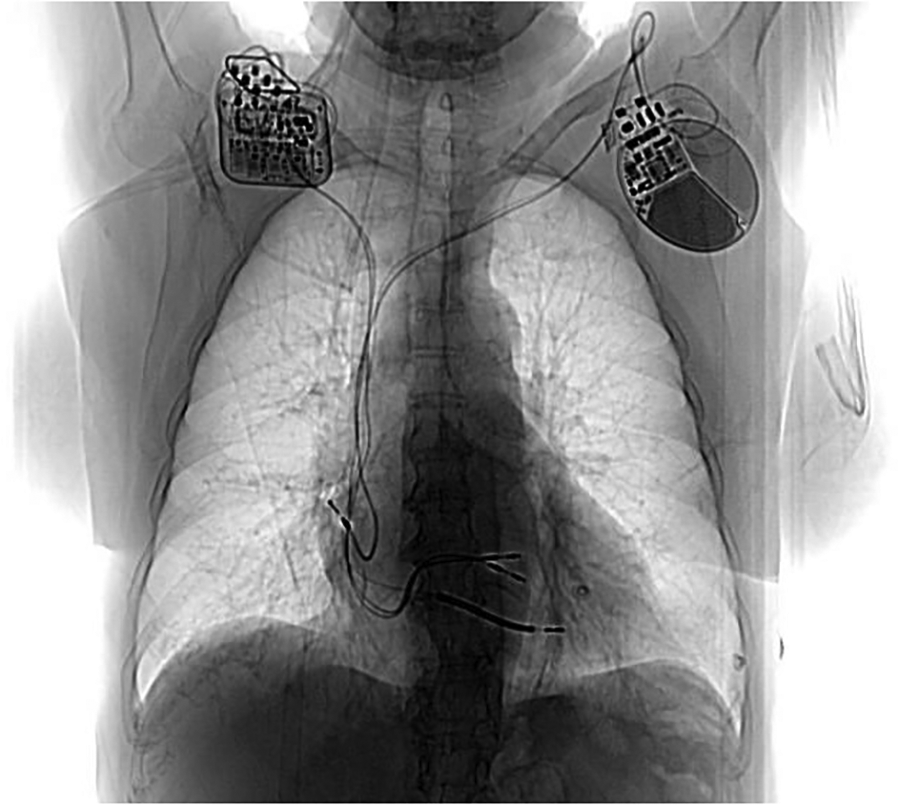

Following informed consent on the benefits, expectations, and potential complications of CCM implantation, in December 2022 the patient underwent implantation of a two-lead CCM, consisting of an Optimizer Smart implantable pulse generator (Impulse Dynamics Inc. Orangeburg, NY, USA) located in the right infraclavicular fossa connected to 2 ventricular pacing leads placed in the interventricular septum (Figure 1). The target area is the lower part of the septal region of the right ventricle, maintaining at least 2 cm separation. Lead positioning is obtained with a Mond type stylet, designed with a primary J curve and a secondary posterior curve. Proper pacing and sensing parameters were confirmed, with no diaphragmatic or chest wall capture and no patient's complain of chest discomfort during high-output stimulation. The device was programmed in OVO-LS-CCM mode with a CCM train of 2 pulses of 7.5 V with a 22 ms duration and a CCM programmed dose of 8 h periods per day. The typical CCM ECG is with spike within QRS refractory period (Figure 2).

Figure 1

Post CCM implant chest X ray. Generator is located in the right infraclavicular fossa and it’s connected to 2 ventricular pacing leads. On the left side the previous dual chamber ICD can be noted.